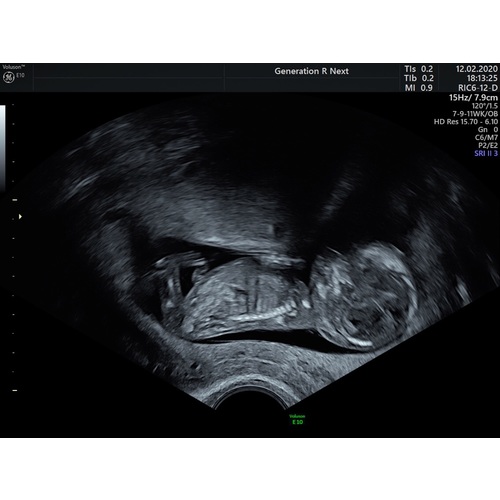

Reactie op Noelloe

11+5. Ik dacht laten we een gokje wagen 😂

Niks te zien nog?

Te klein, te ver, te vroeg..

De navelstreng loopt er ook nog eens langs 😉

Plaats gerust je volgende echo!